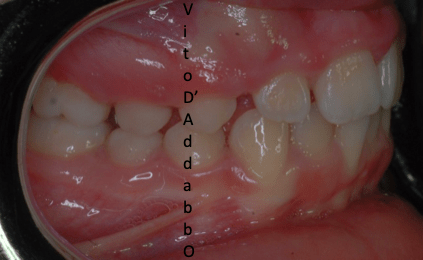

In alcune malocclusioni i denti superiori non coprono adeguatamente quelli inferiori con la presenza in alcuni casi di una beanza fra le due arcate. Questo può essere dovuto ad abitudini viziate come il succhiamento del dito, una deglutizione scorretta, una postura della lingua alterata o un problema scheletrico. In questo esempio il problema è associato ad una terza classe scheletrica.

prima

dopo – fase 1